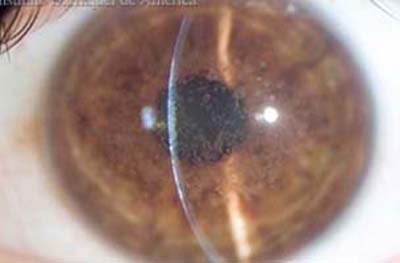

Descompensación de la Córneal Primaria

Distrofia Endotelial de Fuchs, conocida como córnea Guttata por el aspecto de las verrugosidades que aparecen en el endotelio. Con retroiluminación, (reflejo rojo) el aspecto endotelial es el de la plata martillada. Es una entidad familiar hereditaria y progresiva pero que toma décadas para desarrollarse. Produce pérdida de la transparencia de la córnea por incapacidad del Endotelio para mantener el estado de deshidratación corneal.

Los signos y los síntomas de la distrofia se hacen evidentes después de los 50 años con visión borrosa mayor al despertarce que mejora a lo largo del día. A medida que progresa, los periodos de emborronamiento se van haciendo más largos y permanentes.

Descompenzación Corneal

Descompenzación Corneal